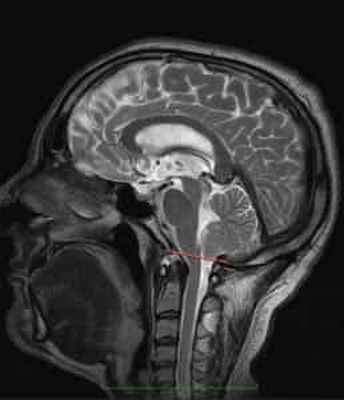

МР-картина ААК II типа – четко визуализируется каудальное смещении нижних отделов червя мозжечка,

продолговатого мозга, а также гидроцефалия